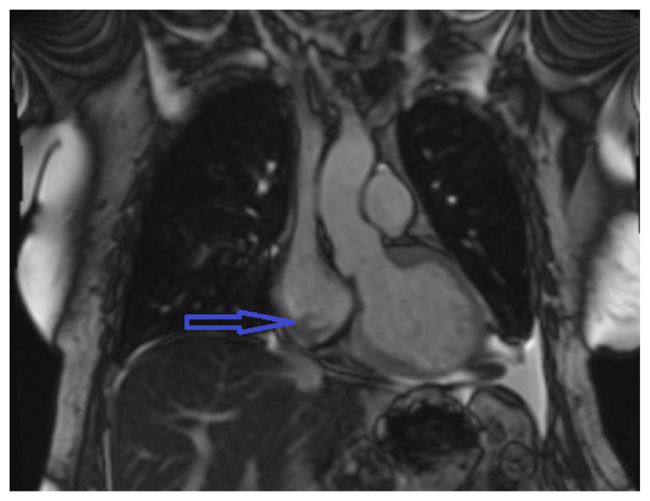

Intradialytic Atrial Fibrillation With Rapid Ventricular Response From Catheter-related Right Atrial Thrombus.

Right atrial thrombus is a rare complication of hemodialysis catheter with an incidence of <6 %. New-onset atrial fibrillation can be the first symptom of catheter-related right atrial thrombus (CRAT) in a patient with long-term dialysis catheter. Therefore, evaluation for CRAT is justified in such scenario. We highlight a case report where a new-onset atrial fibrillation led to the discovery of a right atrial thrombus in a patient with long-term dialysis catheter.